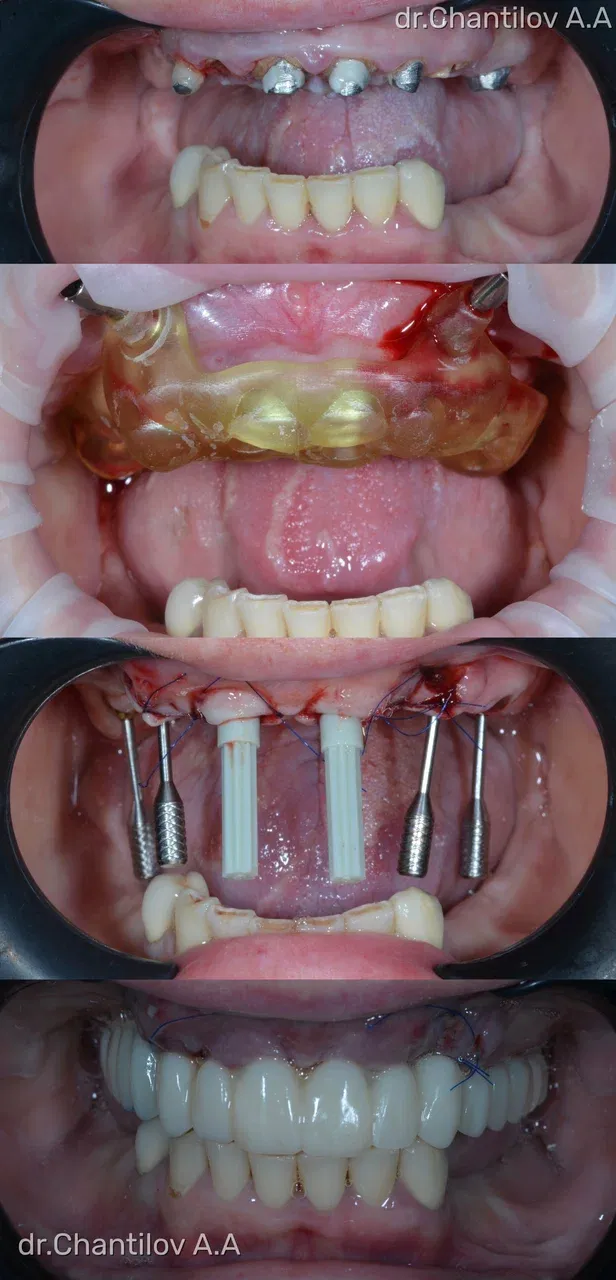

Имплантация зубов челюсти - фото до и после

Изготовление индивидуального шаблона